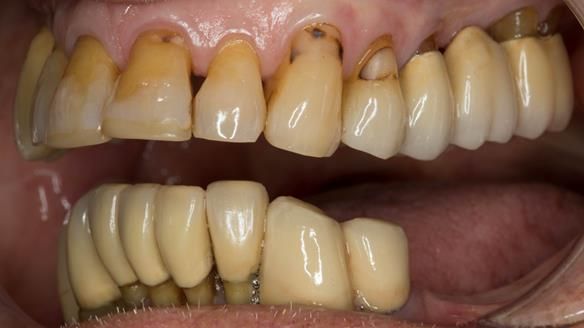

This case was always about function, not aesthetics.

Ken’s teeth were never going to look perfect.

There were stained composites, old restorations, and obvious wear.

That was accepted from the outset.

The way Rowan lengthened the teeth — particularly in the upper RPD — to match the existing gingival recession on the remaining teeth was superb. The dentures sit naturally within the context of the rest of the mouth.